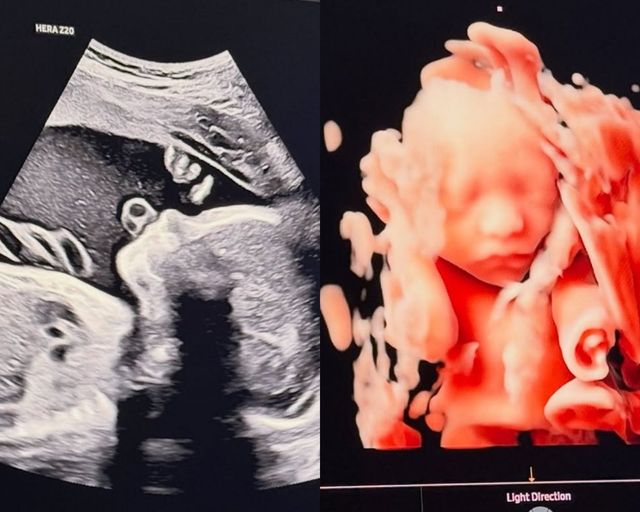

사진=송승현 SNS 사진=송승현 SNS

송승현은 21일 자신의 인스타그램에 “곧 만나자, 우리 햇님이”라는 글과 함께 사진을 게재했다.

공개된 사진에는 태아의 초음파 사진이 담겼다. 송승현을 쏙 빼닮은 듯한 오뚝한 콧날과 또렷한 이목구비가 눈길을 끌었다.